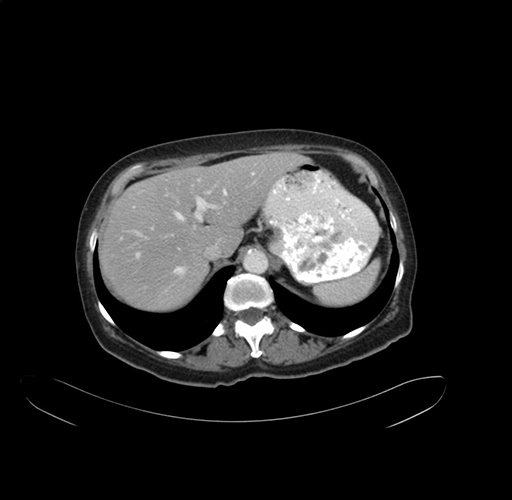

Pre-Chemo: Axial Venous

Pre-Chemo: Coronal Venous